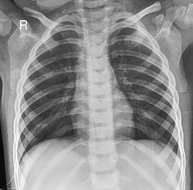

Generally taken as AP for posterior ribs and PA for anterior ribs.

Fig. 7-13 45° RAO above diaphragm—bilateral, right anterior injury (to shift spine away from injury).

• Erect, or recumbent if needed (erect preferred)

• Oblique 45°, rotate spine away from area of interest

• Involved region of thorax is centered to IR with top of IR ≈4 cm (1.5″) above shoulders